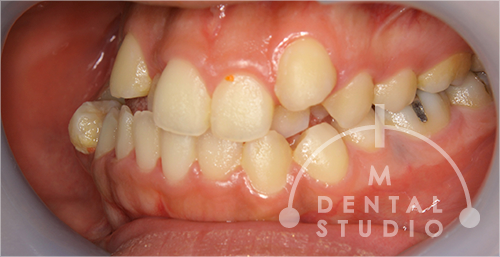

右側から見た写真(術前)

前から4番目の歯は抜きましたが、前歯の裏側にあった2番目の歯は抜かずに、前方(唇側)に出してきました。